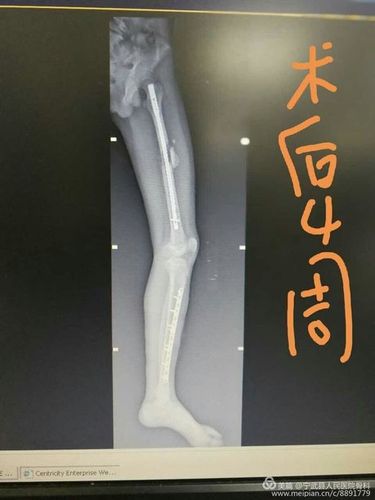

看这例股骨干骨折术后接下来将如何处理?

写美篇 第一例患者为42岁女性,体态偏胖,右股骨干中下段骨折,九个月前

股骨干骨折不愈合次置骨换钉十钢板固定

股骨干骨折髓内钉图片